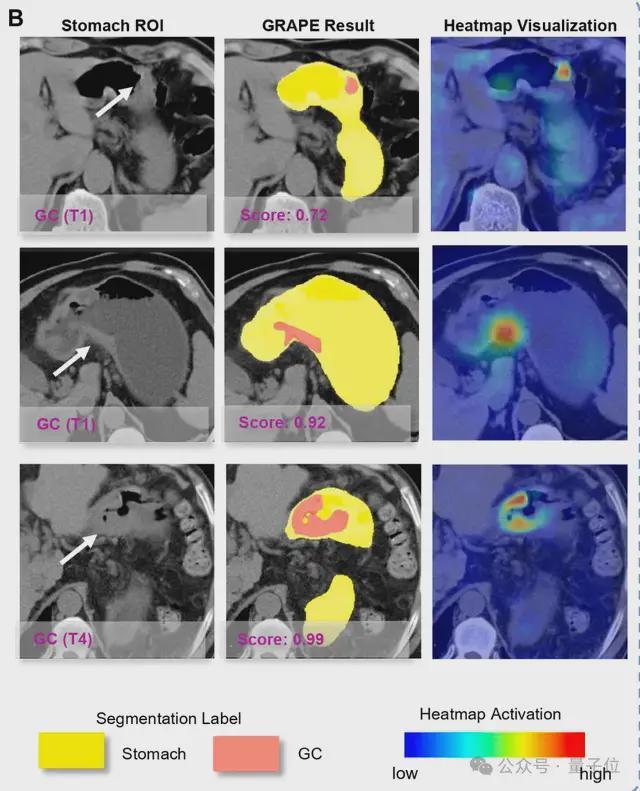

DAMO GRAPE的敏感性和特异性分别达到85.1%和96.8%,相比起人类放射科医生分别提升21.8%和14.0%。

具体把这个AI模型应用在“平扫CT+AI”模式的临床医学上,就是先用AI对腹部平扫CT检查患者初筛,再对AI提示的胃癌高风险人群通过胃镜确诊。

△AI成功从平扫CT识别早期胃癌

△AI能识别各个阶段的胃癌